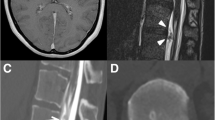

A 72-year-old woman, with no significant past medical history, presented with a 1 year history of thoracic back pain and a 2 week history of progressive lower extremity weakness. Neurological examination revealed MRC grade 3/5 power including and distal to the L2 myotome. She had reduced pin-prick sensation below L1 bilaterally. Reflexes were brisk in the lower limbs and both planters were upgoing. Neurological examination of the upper limbs was normal. Magnetic resonance imaging (Fig. 1) and a CT scan (Fig. 2) demonstrated a central calcified disc herniation at the level T9–T10 level causing spinal cord compression with T2 signal change in the spinal cord. The calcified disc prolapse occupied more than 60 % of the cross-sectional area of the spinal canal.